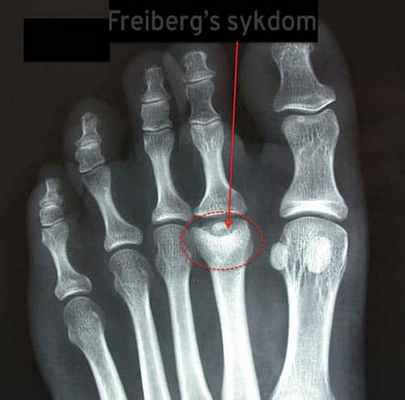

Радиодиагностическое исследование показывает линию перелома, более или менее заметную, расширение суставной щели. Головка сплюснутая и расширена в развитой стадии некроза.

Основываясь на результатах рентгенологического исследования, выделяют пять фаз заболевания.

1 фаза – появляется трещина в головке плюсневой кости.

2 фаза – центральная часть головки рассасывается, а сама головка уплощается. Начинается слущивание хряща.

3 фаза – продолжается деформация всей головки, плюсневая кость уменьшается в 2-3 раза, приводя к укорочению пальца.

4 фаза – возникают переломы головки и кости, приводя к возникновению в полости сустава свободных тел.

5 фаза – головка плюсневой кости расширена и уплощена, суставная щель расширена, возникают грубые вторичные артрозные деформации.

Рентген болезни Фрейберга:

- На картинке выше мы видим остеонекроз (отмирание костной ткани) второй плюсневой кости. Характерный признак болезни Фрейберга.

Диагностика

Диагноз болезни Фрейберга - Келера II может быть подтвержден после клинического обследования с помощью рентгенограмм. На рентгенограммах ног могут наблюдаться незначительные изменения в начале проявления заболевания, характеризующиеся расширением суставного пространства. Расширение может наблюдаться в течение 3-6 недель после появления симптомов. По мере прогрессирования заболевания происходит увеличение плотности кости в субхондральной области и уплощение плюсневой головки.